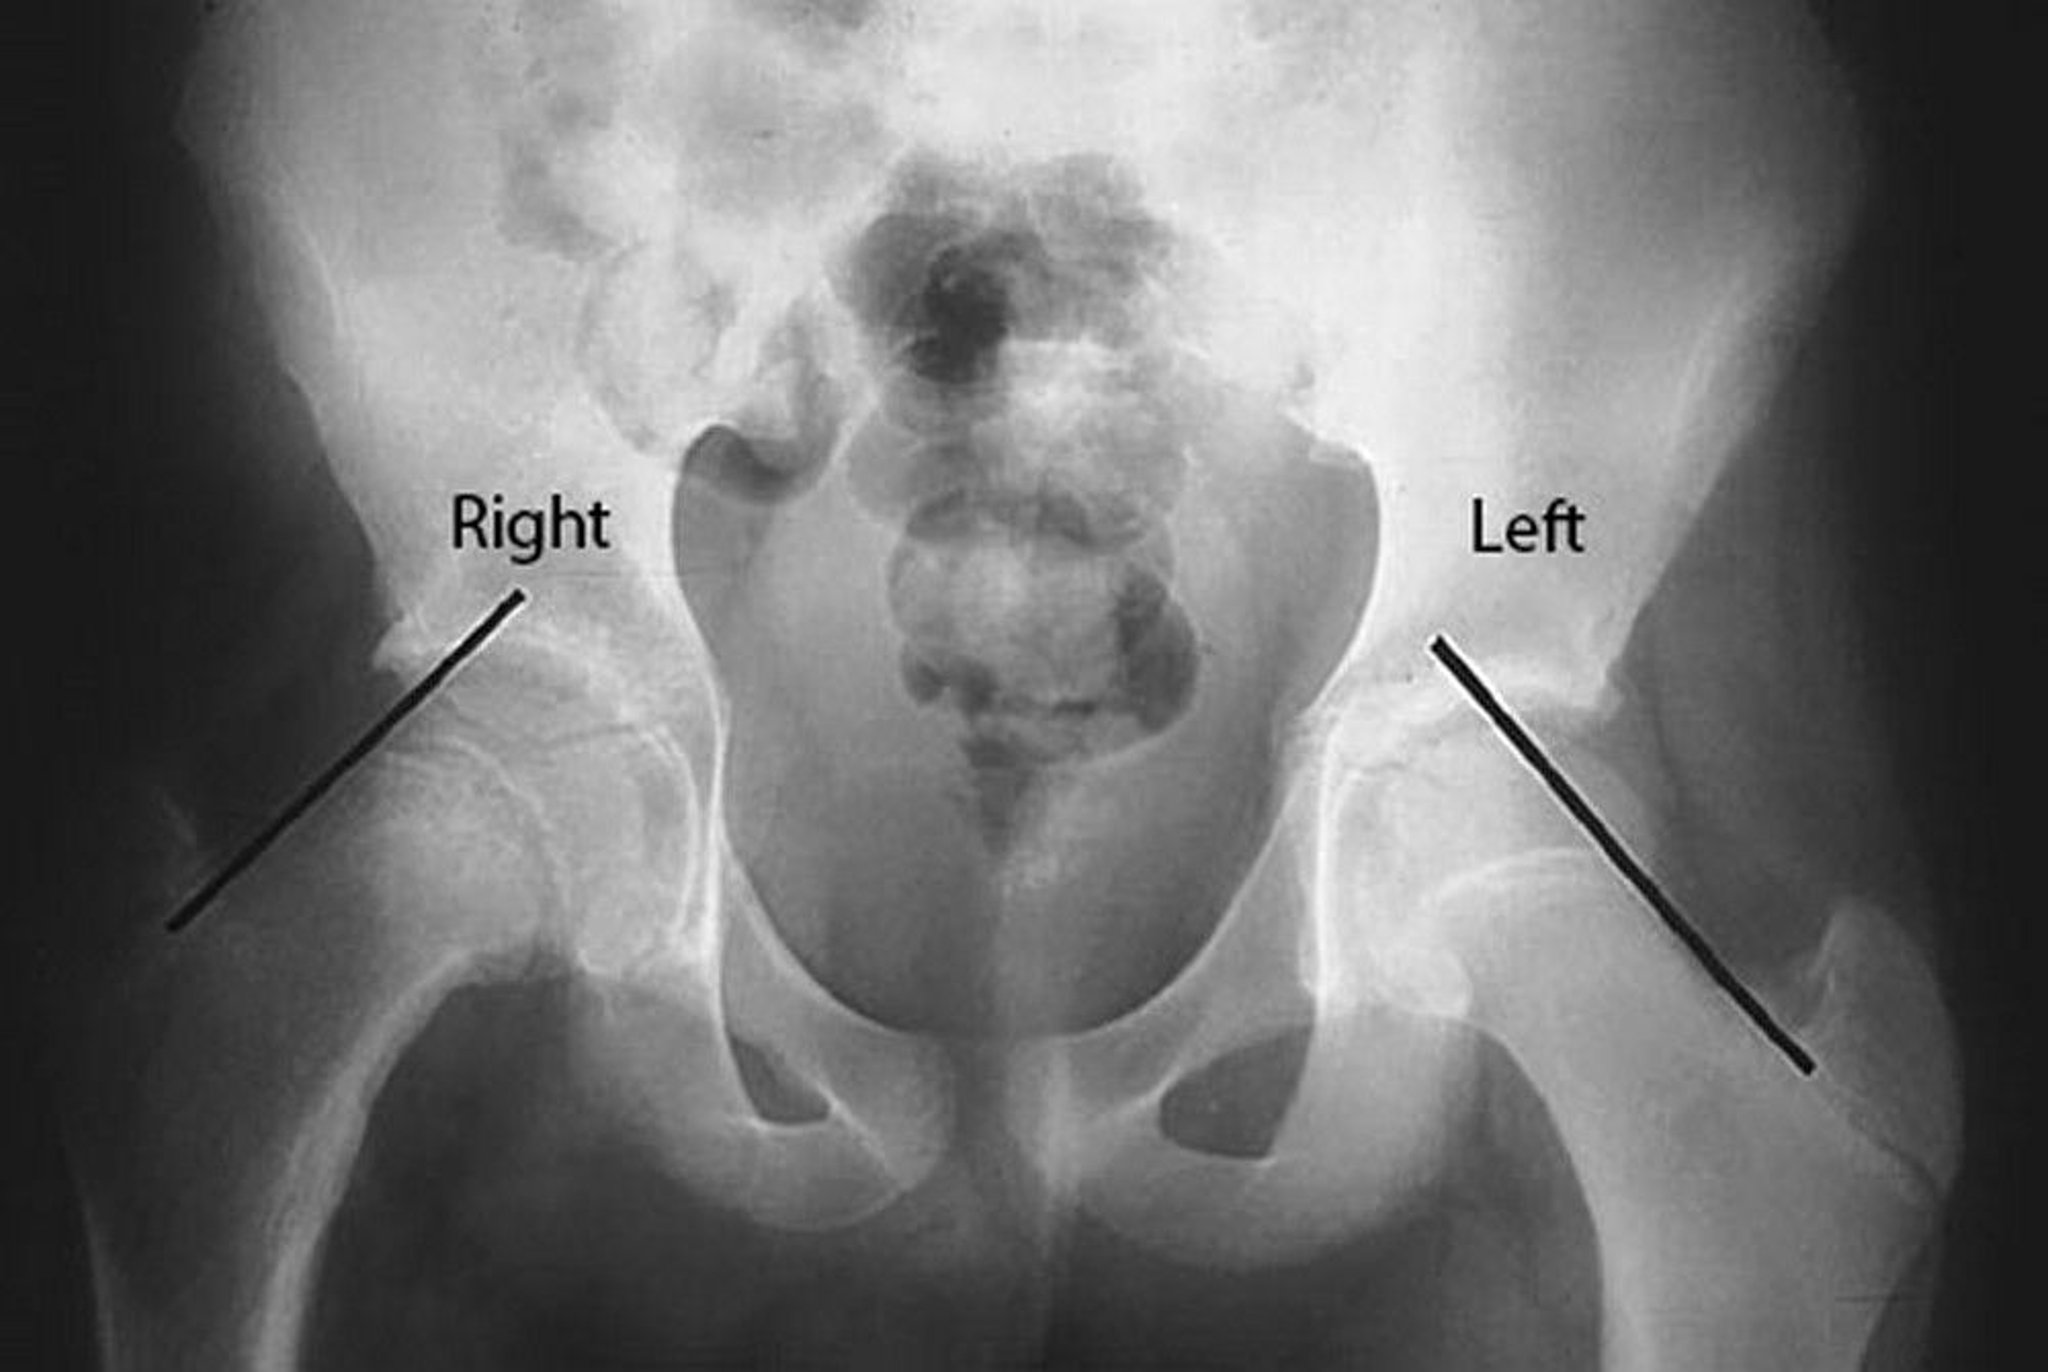

Slipped Capital Femoral Epiphysis (SCFE)

Klein lines are drawn on the superior border of the femoral neck in this patient with slipped capital femoral epiphysis (SCFE) of the right hip. Note that the femoral head is below the Klein line on the affected right side, whereas a significant portion of the femoral head is above the Klein line on the unaffected left side.